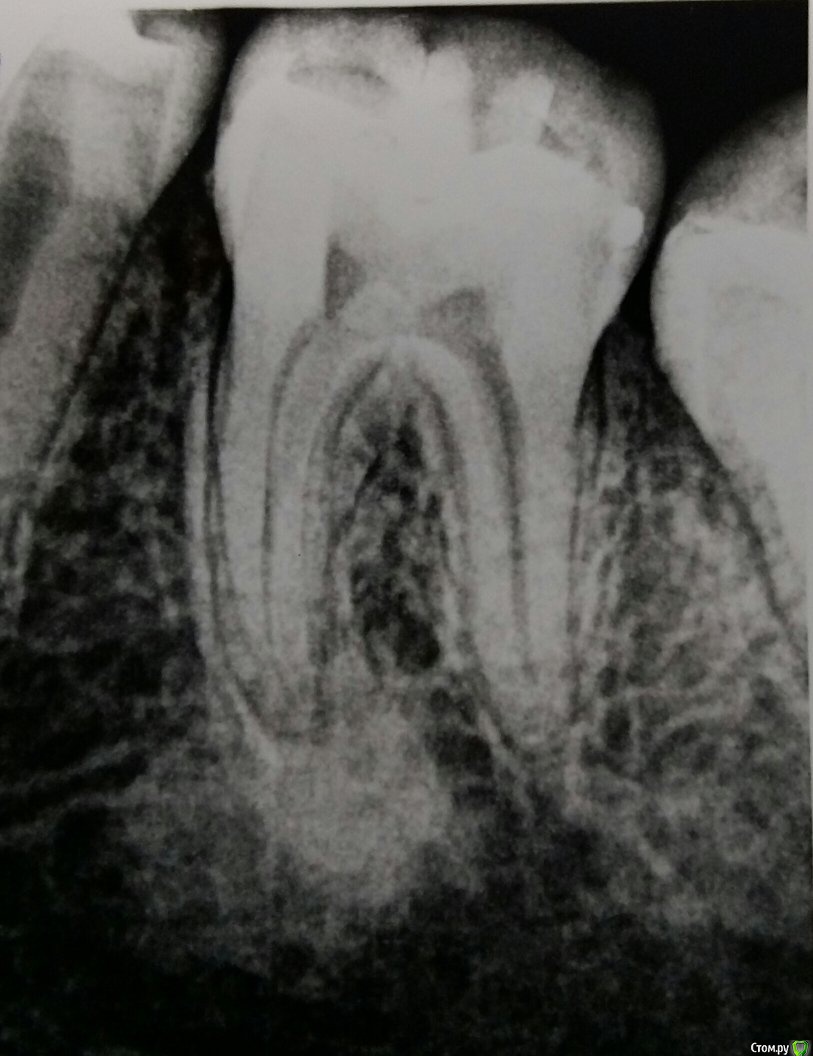

elen_rein Опубликовано 15 апреля, 2015 Поделиться Опубликовано 15 апреля, 2015 Здравствуйте!очень нужен совет.На рентгене стоматолог-ортопед обнаружил воспаление под корнем зуба,похожее на кисту,посоветовал обратиться к хирургу.Ранее зуб не лечили,он никогда не беспокоил.Но сейчас появилась ноющая боль. Подскажите пожалуйста какие есть варианты лечения данного зуба? Ссылка на комментарий

Гарриевич Опубликовано 15 апреля, 2015 Поделиться Опубликовано 15 апреля, 2015 это как бы и не киста, а наоборот =)надо выявить причину боли, а с этой "некистой" к хирургу идти не надоуберите контраст на снимке и выложите еще раз 1 Ссылка на комментарий

elen_rein Опубликовано 15 апреля, 2015 Автор Поделиться Опубликовано 15 апреля, 2015 это как бы и не киста, а наоборот =)надо выявить причину боли, а с этой "некистой" к хирургу идти не надоуберите контраст на снимке и выложите еще разСпасибо за ответ!!уменьшила немного контрастность.С зубом обращаться к терапевту,правильно? Ссылка на комментарий

DmitrySH Опубликовано 15 апреля, 2015 Поделиться Опубликовано 15 апреля, 2015 Путь терапевт посмотрит на предмет наличия кариеса на контактах Ссылка на комментарий

Гарриевич Опубликовано 15 апреля, 2015 Поделиться Опубликовано 15 апреля, 2015 Спасибо за ответ!!уменьшила немного контрастность.С зубом обращаться к терапевту,правильно?Обратитесь к грамотному терапевту и все решится =) Ссылка на комментарий